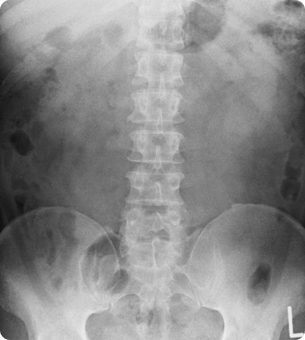

そのため、「レントゲン・MRI・エコー(超音波)」といった最新の画像診断機器を駆使し、原因を徹底的に明らかにします。

- X線